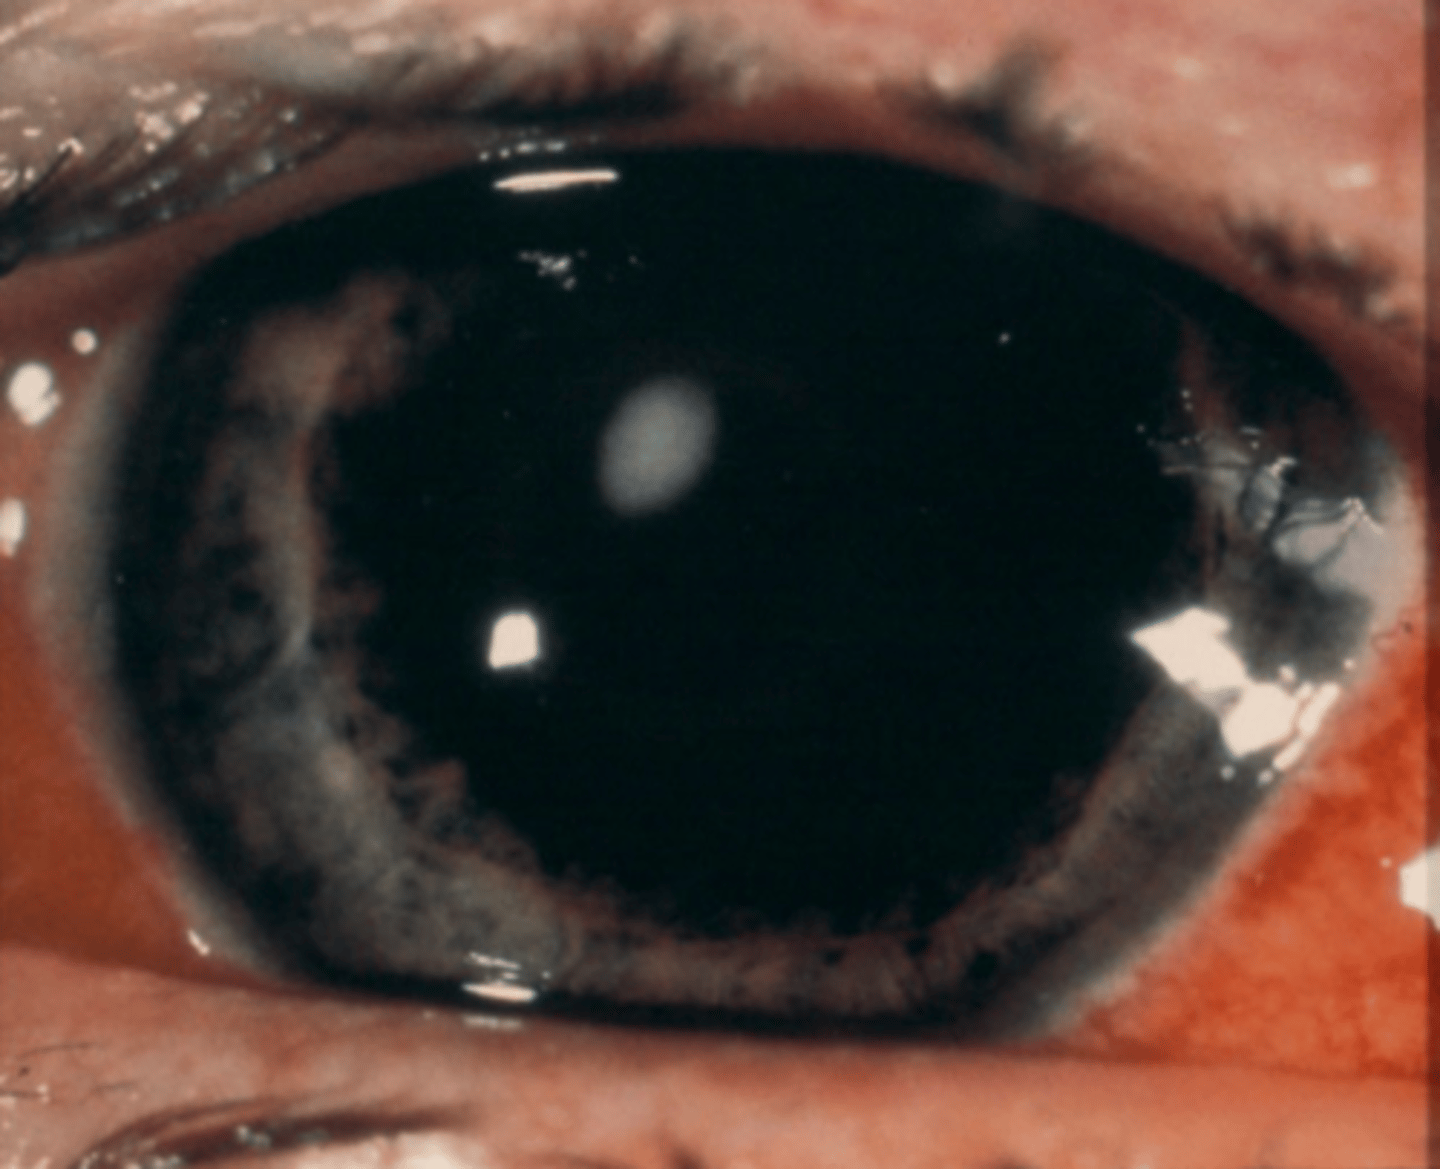

What ocular condition is shown here?

multiple, peripheral corneal infiltrates with localized paralimbal injection

How would you describe what we see on slit lamp here?

marginal keratitis

What is most likely the diagnosis of the patient shown here? (not a CL wearer)

staph hypersensitivity reaction (inflammatory) due to poor lid hygiene

What is the cause of marginal keratitis?

exotoxins (from staph) deposit on cornea where the lid margin intersects

What causes corneal infiltrates (collection of WBCs) in marginal keratitis?